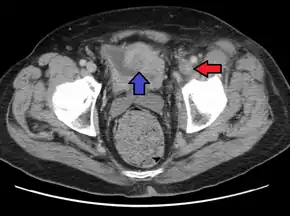

Deep vein thrombosis of the left external iliac in a person with bladder cancer resulting in this condition.

PCD is best diagnosed with contrast venography, but venous duplex ultrasonography is used more commonly. Magnetic resonance and computed tomography venography can also be used.[4]